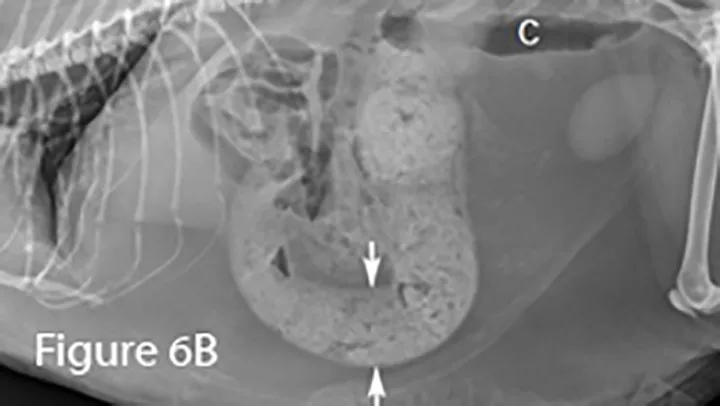

Lateral (Figure 6B) and ventrodorsal (Figure 6C) abdominal radiographs of severely distended segment of bowel identified sonographically and properly diagnosed as severe small intestinal obstruction (arrows). Of note, there is fecal-like material in the small intestine. An ileocecocolic mass was diagnosed during exploratory laparotomy. This mass was apparently obscured by gas during ultrasound examination. (C = colon)

This older cat presented for vomiting; ultrasonography was the first diagnostic modality.

Ultrasound image of an enlarged intestine (arrows) showing large amount of reverberation artifact (arrowheads) caused by luminal gas. This prohibits visualization of the far wall of this loop of bowel. The ultrasound impression was a distended colon.